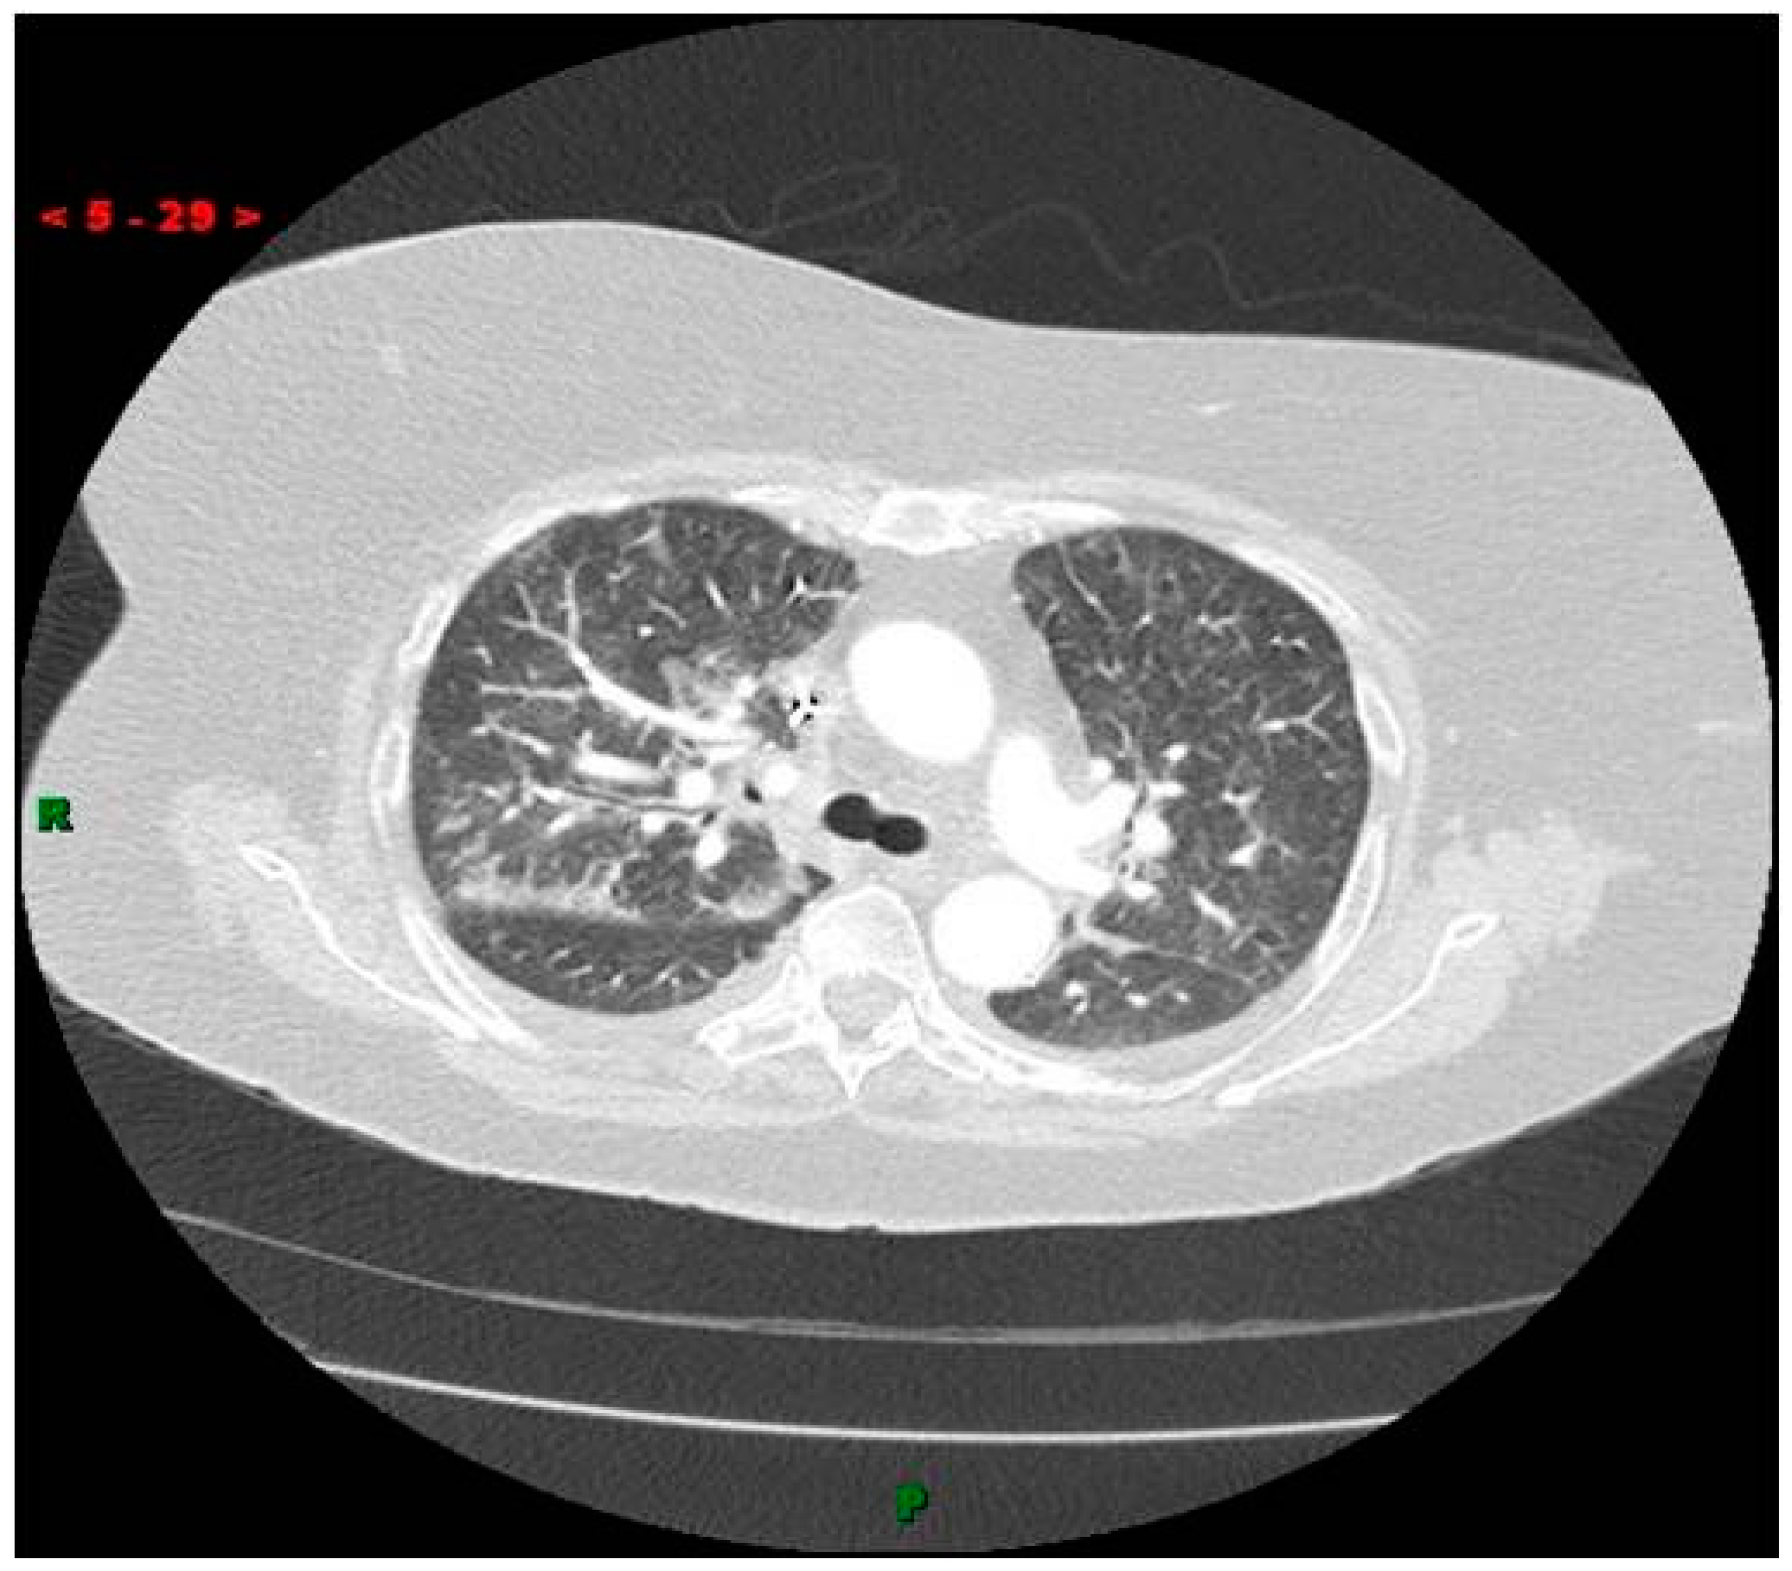

- Choe, D.H.; Marom, E.M.; Ahrar, K.; Truong, M.T.; Madewell, J.E. Pulmonary embolism of polymethyl methacrylate during percutaneous vertebroplasty and kyphoplasty. Am. J. Roentgenol. 2004, 183, 1097–1102. [Google Scholar] [CrossRef] [PubMed]

- Duran, C.; Sirvanci, M.; Aydoğan, M.; Ozturk, E.; Ozturk, C.; Akman, C. Pulmonary cement embolism: A complication of percutaneous vertebroplasty. Acta Radiol. 2007, 48, 854–859. [Google Scholar] [CrossRef] [PubMed]

- Krueger, A.; Bliemel, C.; Zettl, R.; Ruchholtz, S. Management of pulmonary cement embolism after percutaneous vertebroplasty and kyphoplasty: A systematic review of the literature. Eur. Spine J. 2009, 18, 1257–1265. [Google Scholar] [CrossRef] [PubMed]